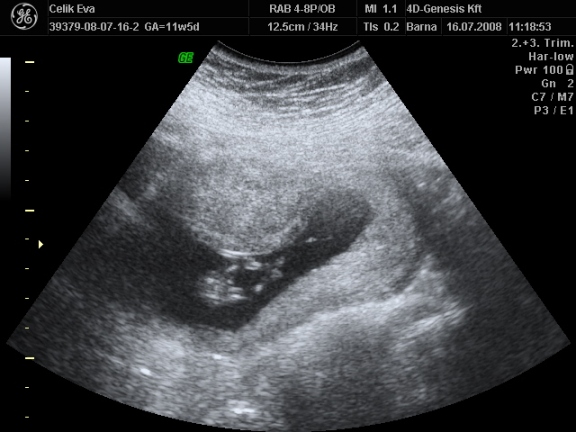

a képek:

3d-s babafotók:

Kép